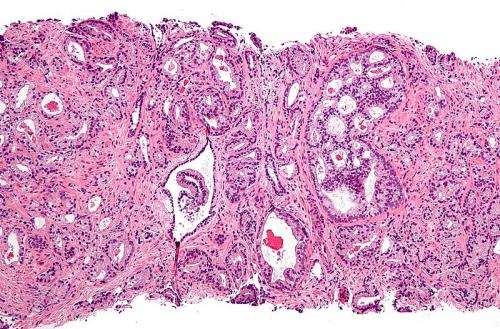

“Historically, prostate cancer has been very resistant to checkpoint inhibitors because it is immunologically cold with few tumor-infiltrating T cells,” said principal investigator Padmanee Sharma, M.D., Ph.D., professor of Genitourinary Medical Oncology and Immunology. “These results suggest that a combination approach to increase T cell infiltration and then block inhibitory pathways may be a useful strategy for treating these patients. Going forward, we plan to optimize the schedule and dosing to improve the safety profile.”

In previous research published in Nature Medicine, Sharma and colleagues discovered that prostate cancers deploy multiple mechanisms to dampen the anti-tumor immune response. Although anti-CTLA-4 therapy could recruit T cells, the tumor-infiltrating T cells elicited compensatory inhibitory pathways, including immune-suppressing proteins PD-L1 and VISTA.